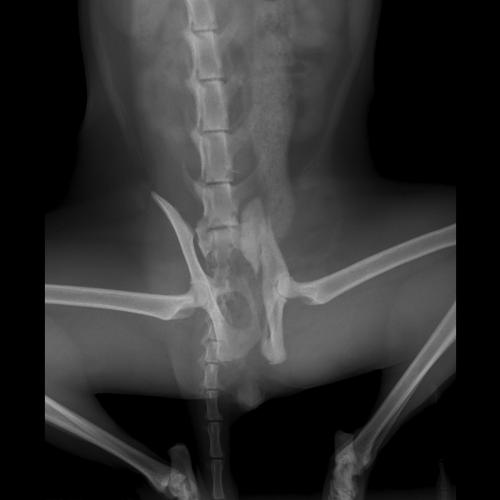

Gatto Frattura Bacino Clinicaveterinaria Org Forum Source: clinicaveterinaria.org

Ciao a tutti. Mariarosaria91 Buonasera stanotte hanno investito il mio gatto di un anno procurandogli una frattura del bacino. Rintracciato dai militari è stato denunciato. Ciao a tutte 11 anni fa a causa di un incidente stradale ho subito una frattura ileo ischio pubica in 4 punti. Della branca ischio pubica delle spine iliache antero-superiori e inferiori.

Iliaco ischio e pube che sono saldati insieme. Mariarosaria91 Buonasera stanotte hanno investito il mio gatto di un anno procurandogli una frattura del bacino. Frattura bacino pareri. Ho la fortuna di non dover fare riabilitazione perché non mi sono rotta unarticolazione. Ora mi chiedevoci saranno problemi per un parto naturaleLa mia gine mi ha detto che magari è meno elastico di un bacino normale ma che comunque visto che è anche il primo figlio non se ne parla di cesareo meno male.

Non sono qua per farmi fare la morale sono uscito da una frattura scomposta del bacino che mi ha tenuto fermo 2 mesi e mezzo per lavoro alle 3 di notte devo farmi questa 30ina di km per rientrare e sono qua per imparare quello che non ho mai imprato sulle bici in particolar modo le ebike. Entità e tipo della frattura si potranno capire solo dalla radiografia. Frattura del bacino 30 giorni a letto e dopo. Mariarosaria91 Buonasera stanotte hanno investito il mio gatto di un anno procurandogli una frattura del bacino. Eusebio clinica veterinaria asola clinica veterinaria mantova clinica veterinaria provincia di mantova clinica veterinaria cremona c.

Forum Ragazze Fuori di Seno SpazioUtenti. Ho la fortuna di non dover fare riabilitazione perché non mi sono rotta unarticolazione. Per ulteriori approfondimenti si può ascoltare la puntata del 24 aprile scorso della rurbica Sport e Salute a cura del Prof. Mariarosaria91 Buonasera stanotte hanno investito il mio gatto di un anno procurandogli una frattura del bacino. Qualche dolorino lo avverto ma se è vero che non.